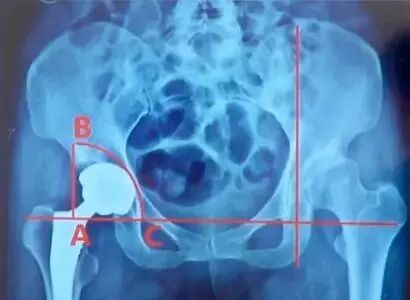

Hubard法:

①在X线上两侧闭孔上缘连线与通过髋臼外上角垂线的交点为A;

②点A线上1/4骨盆高度处为B,再在闭孔连线上作点C,使AC=AB;

③以A为中心,以AB为半径做圆弧BC,正常髋臼应在此等腰三角扇形内。